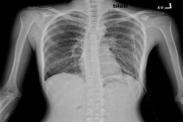

老年人厭氧菌性肺炎癥狀

• 老年人厭氧菌性肺炎